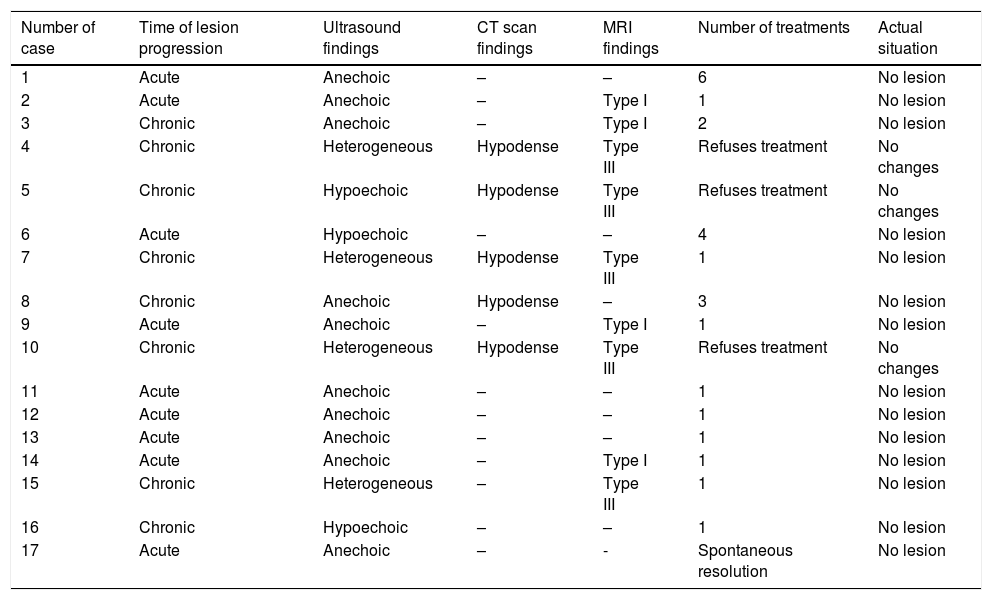

Material and methodsWe retrospectively reviewed 17 patients (11 men and 6 women; mean age, 56.1 years, range 25–81 years) diagnosed with Morel-Lavallée lesions in two different departments. All patients underwent ultrasonography, 5 underwent computed tomography, and 9 underwent magnetic resonance imaging. Percutaneous treatment with fine-needle aspiration and/or drainage with a 6–8F catheter was performed in 13 patients. Two patients required percutaneous sclerosis with doxycycline.

ResultsAll patients responded adequately to percutaneous treatment, although it was necessary to repeat the procedure in 4 patients.

ConclusionsRadiologists need to be familiar with this lesion that can be treated percutaneously in the ultrasonography suite when it is not associated with other entities.